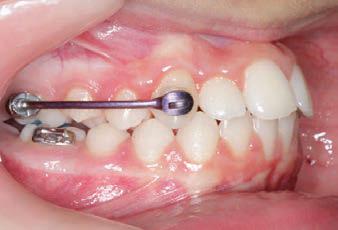

The SAGITTAL FIRST™ Philosophy is a time-tested approach that standardises, simplifies, and shortens Class II and Class III treatment times. It employs the Carriere Motion 3D Appliance to treat the AP dimension at the beginning of treatment before placing brackets or aligners. By resolving the most difficult part of treatment first, you can achieve a Class I platform in 3 to 6 months, shortening total treatment time by a minimum of 6 months1. You know how excited patients and parents become when you mention shorter treatment times.

INITIAL - 4/4/18

PROGRESS 1 - 26/9/18 - Class I platform accomplished in 5.75 months with Motion 3D COLOR Appliance